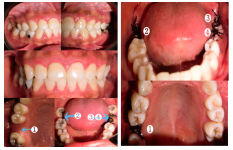

图2 术前术后CBCT影像

该患者因上颌多颗后牙缺失数年,伴随牙槽骨严重吸收、上颌窦底骨量严重不足,同时口内存在残根、阻生智齿,曾被判定为常规种植方案无法实施,种植难度极高。为最大限度减少患者创伤与往返就诊负担,阿坝州人民医院口腔科团队术前通过口腔CBCT完成全维度解剖结构评估,精准测算骨量数据,量身定制了“一站式”微创种植方案。

得益于上述核心技术的综合应用,手术全程术野清晰,未出现上颌窦黏膜穿孔等并发症,4颗种植体均达到理想的初期稳定性。相较于传统方案需3-4次手术、近半年的治疗周期,本次一站式手术不仅突破了患者“无种植条件”的限制,更极大降低了手术创伤,术后患者反应轻微,恢复情况良好,真正实现了微创、高效、安全的种植修复。